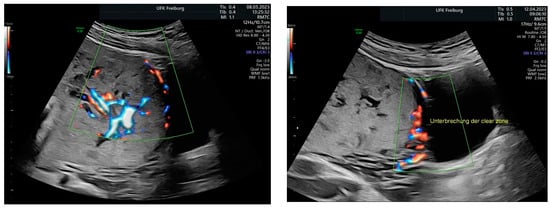

Sonographic findings (Figure 11):

Figure 11.

Increased placental blood flow on 2D ultrasound. Red color represents increased placental blood flow moving to the transducer; blue color represents placental blood flow moving leaving away from the transducer.